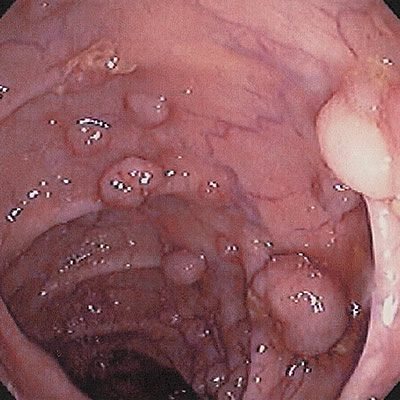

- Ворсинчатый вид. Эти кишечные полипы разрастаются на широкой площади, образуя ковер, поскольку покрыты ворсинками. Из них 40% могут перерасти в злокачественную опухоль.

- Ворсинчатыми. Полипы этого вида при разрастании способны образовать своеобразный ковер на стенках пораженной ими кишки. Вероятность их озлокачествления также составляет не менее 40%.